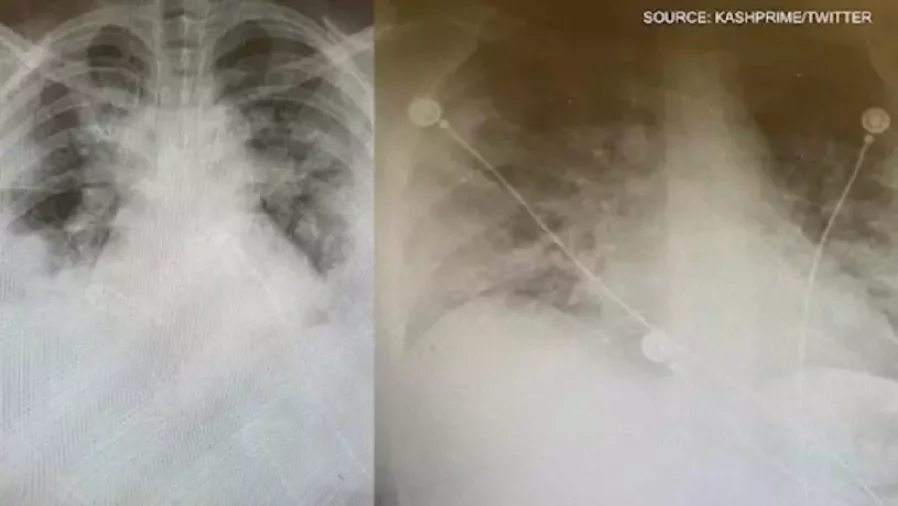

加拿大一名多伦多急症室医生展示了2张肺部充满液体的图片,显示冠病对年轻人的毁灭性损害。

其中1张图片显示的是一个30岁的人的肺部,以及另一名本来健康的35岁教师,从学生身上感染了英国变种冠病。两人都被送进了深切治疗部。